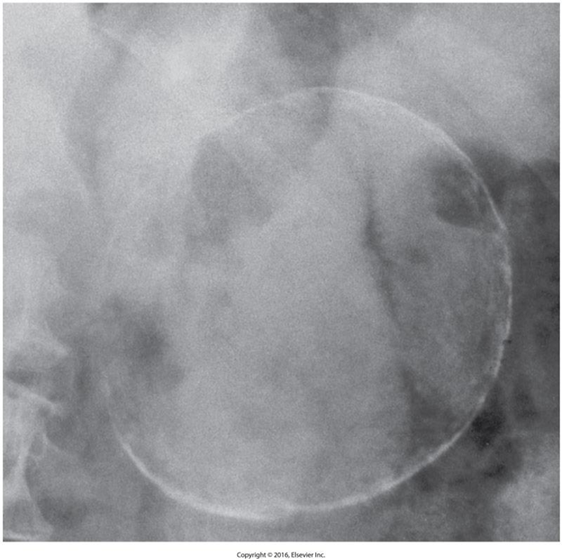

Pancreatic Pseudocyst

is defined as fluid-filled cavity.

They occur due to inflammation, necrosis, or hemorrhage.

Causes:

Acute pancreatitis

Trauma